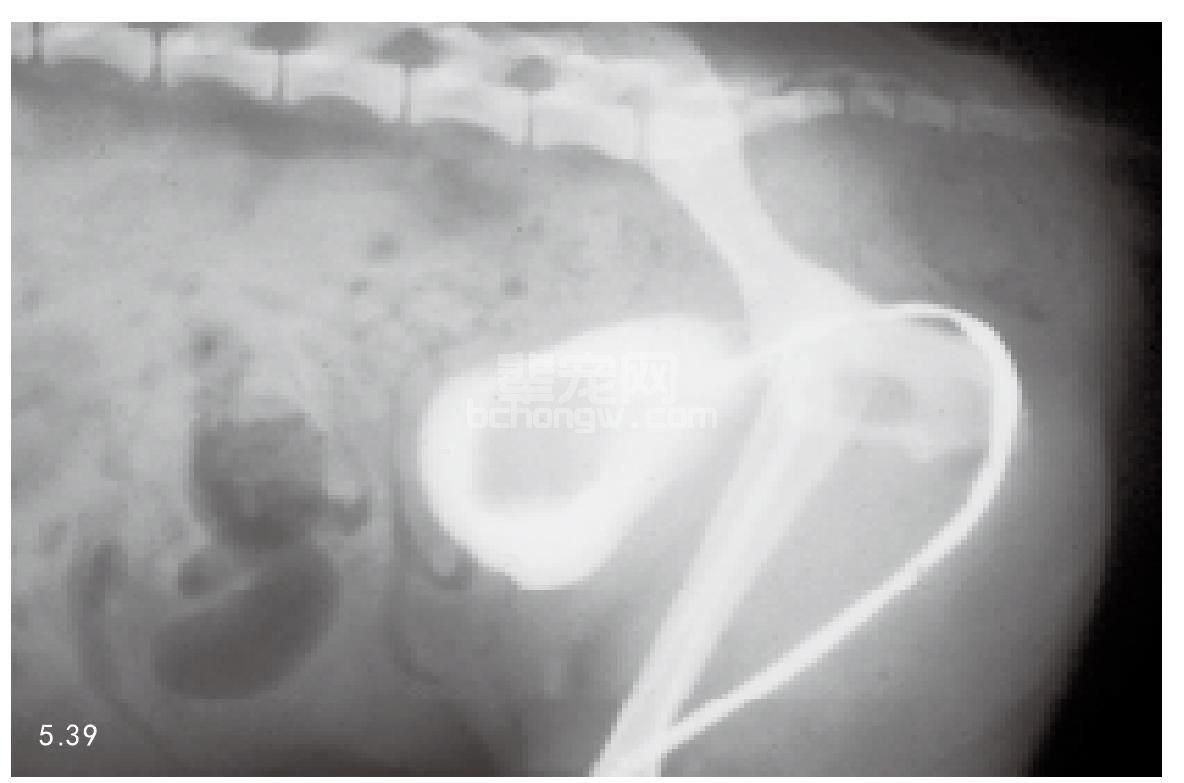

图5.39 约克夏 门静脉系统分流引起的尿酸铵结石的膀胱造影图像。

尿酸铵尿结石发生的危险因素,包括大麦町犬和其他某些品种犬的肝脏尿酸酶活性降低,犬患有先天性门静脉系统分流。这两种情况下,尿酸盐分泌量升高。

诊断 尽管临床表现可以提示结石的大体位置,但是对于泌尿道结石及其数量、大小和位置一般使用X线和超声波检查来确诊(图5.37和图5.38)。使用X线、造影,包括静脉肾盂造影、膀胱造影和逆行性尿道造影来诊断(图5.39)。